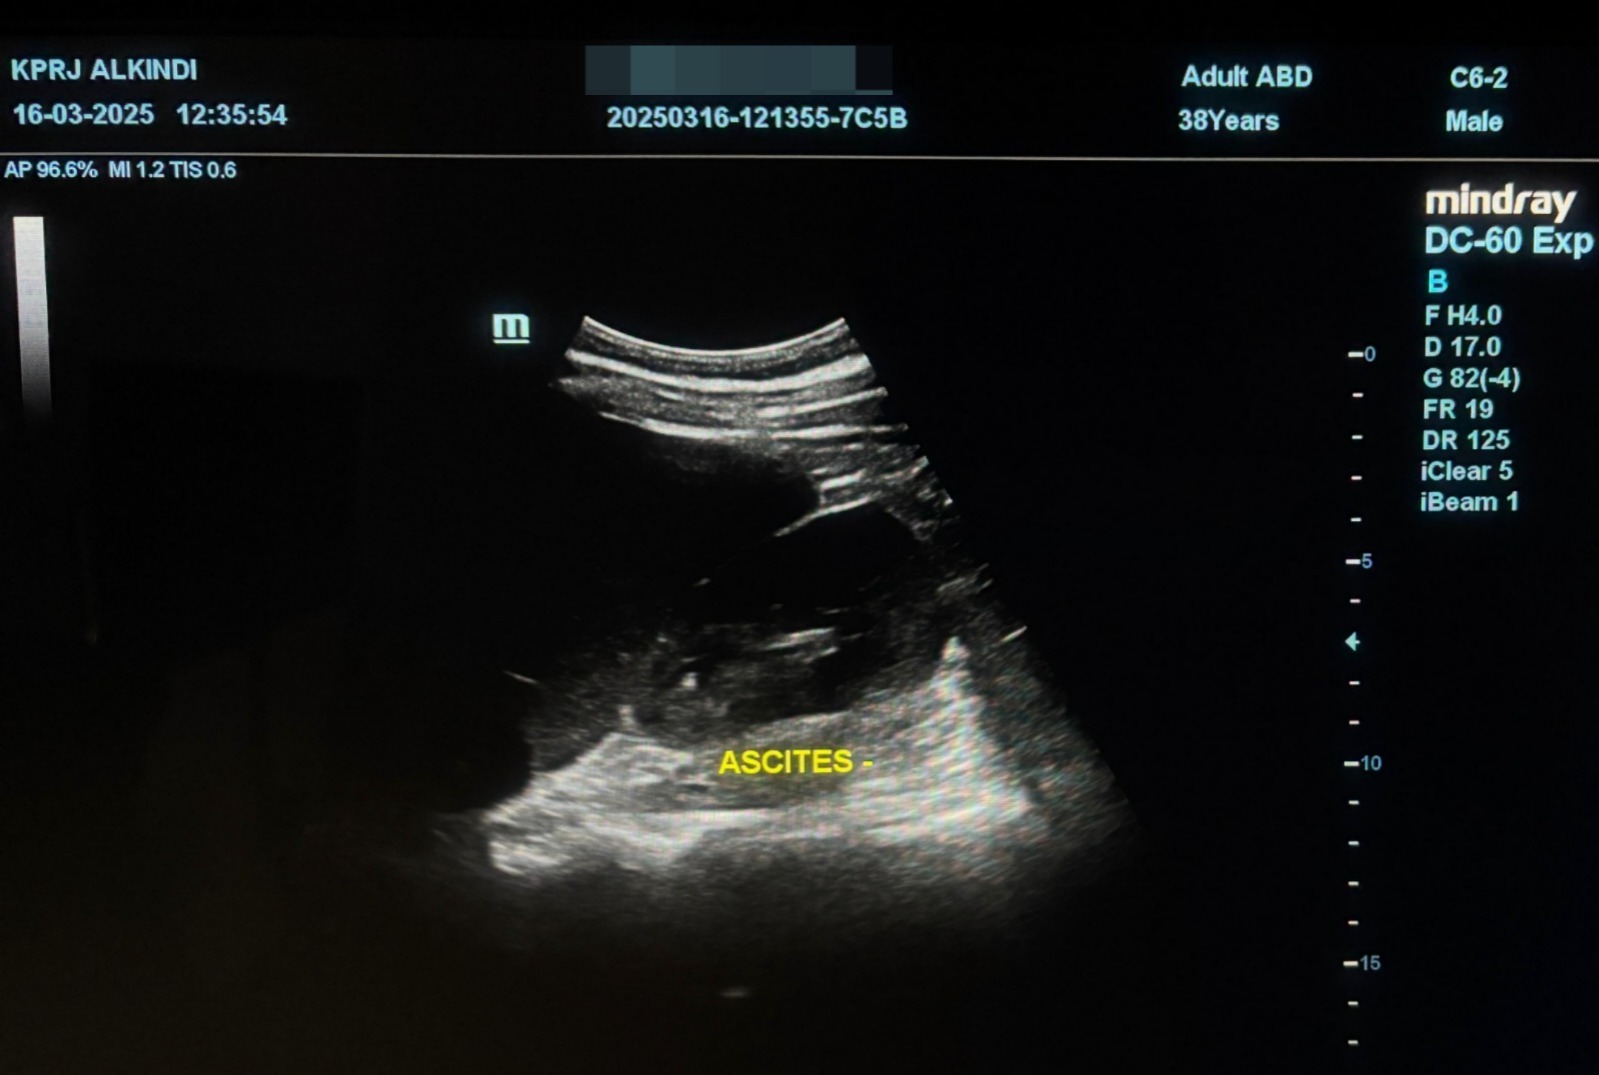

Pada pemeriksaan USG Abdomen 16-03-2025 tidak didapati akumulasi cairan pada kantung paru( efusi) dan juga kantung perut (ascites)